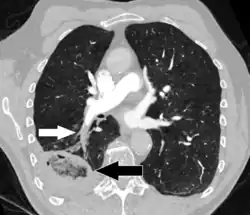

On CT scan, pulmonary emboli can be classified according to the level along the arterial tree. -

Segmental and subsegmental pulmonary emboli on both sides -

CT pulmonary angiography showing a "saddle embolus" at the bifurcation of the main pulmonary artery and thrombus burden in the lobar arteries on both sides

-

Pulmonary embolism (white arrow) that has been long-standing and has caused a lung infarction (black arrow) seen as a reverse halo sign